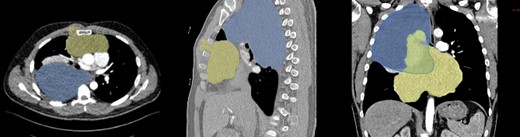

During examination, physicians observed a parasternal swelling, prompting computed tomography (CT) scan (Fig. 2) due to the patient’s extensive medical history and new symptoms. The scan revealed a large 22 cm hypodense lesion in the upper right thorax, partially compressing the superior vena cava and vena subclavia dextra. The lesion showed extensive contact with the trachea and esophagus without signs of infiltration, along with adjacent atelectasis of the upper and middle lobes. Another mass, 20 cm in size, was discovered in the anterior mediastinum, extending into the sternum and musculus pectoralis major. These tumors exhibited no postcontrast enhancement or calcification. Strong suspicion of secondary or metastatic liposarcoma prompted scheduling surgery after presenting the case at a multidisciplinary meeting. Veno–veno extracorporeal membrane oxygenation was planned on standby due to the inability of preoperative imaging to rule out central vessel infiltration.